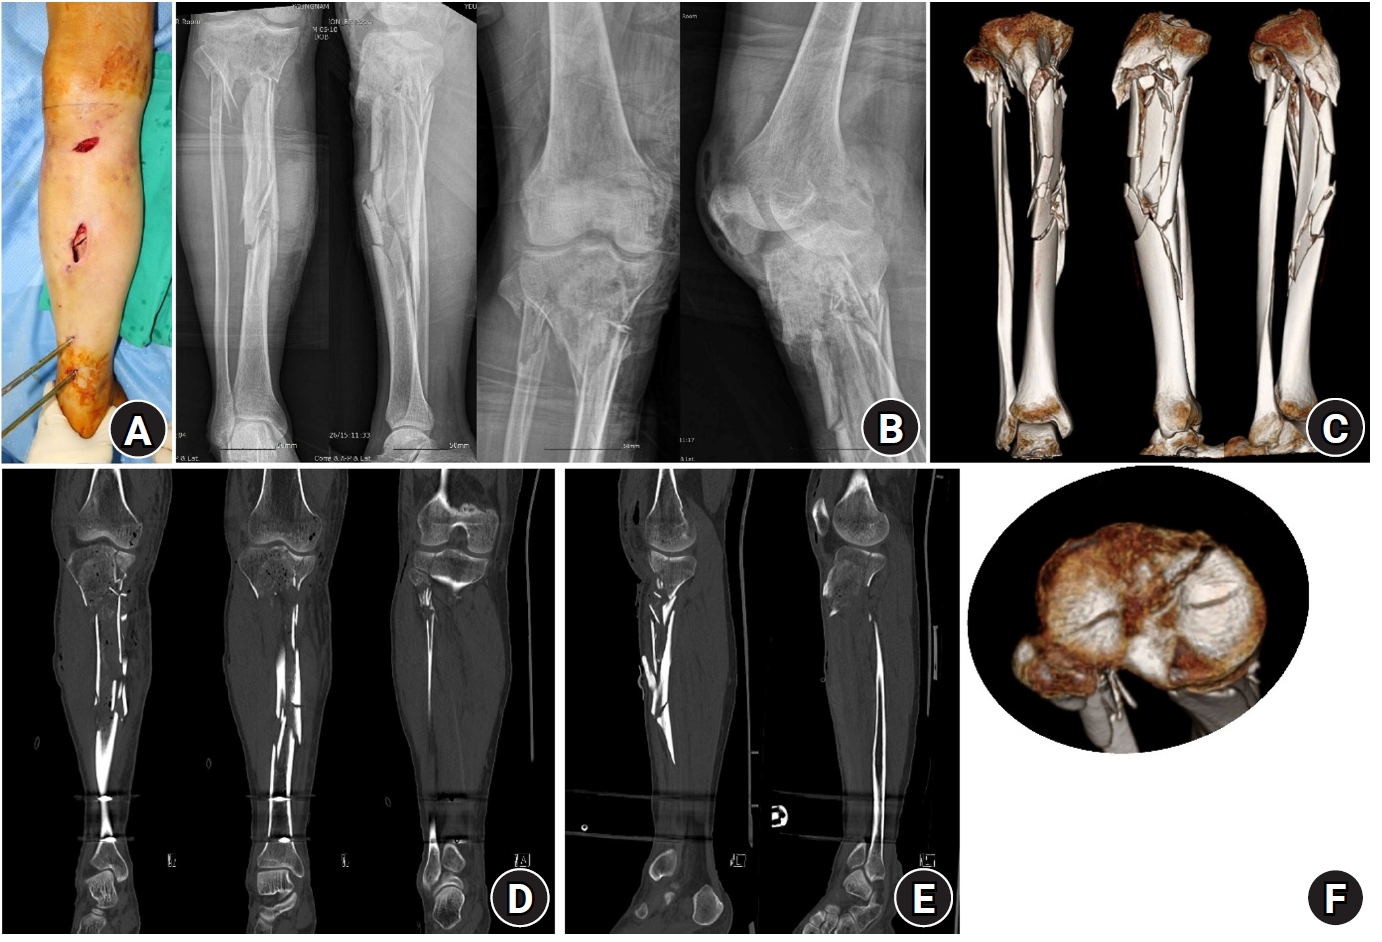

Fig. 1.

Preoperative photographs and imaging studies. (A) Clinical photograph showing multiple open wounds on the anteromedial aspect of the lower leg. (B) Plain radiograph of a complex tibial plateau-to-diaphysis fracture. (C) Three-dimensional computed tomography (3D-CT) image revealing a comminuted plateau-to-diaphysis tibial fracture. (D) Coronal CT image demonstrating a bicondylar tibial plateau fracture. (E) Sagittal CT image showing posterolateral and anteromedial tibial plateau fractures. (F) 3D-CT image illustrating the overall fracture morphology of the tibial plateau.

Case 1

A 54-year-old male patient presented after a motor vehicle accident with multiple open wounds and a complex right-sided tibial plateau-to-diaphysis fracture (Fig. 1). On the contralateral side, he sustained multiple fractures involving the femoral neck and shaft. On the day of injury, initial management included open wound debridement and negative-pressure wound therapy, followed by external fixation of the right tibial plateau and diaphyseal fractures. Definitive surgery for the right tibial plateau-to-diaphysis fractures was performed 8 days after injury, during which a rim plate-assisted NPC technique was planned. This approach was employed because the patient had multiple open wounds on the anteromedial aspect, and dual plating could have exposed the medial plate or require flap coverage. Furthermore, the presence of multiple contralateral limb injuries inhibited partial weight bearing. Once weight bearing began, the injured tibia would bear the full weight from the start. Therefore, the fixation construct must be strong enough to allow immediate full weight bearing to enable early rehabilitation.